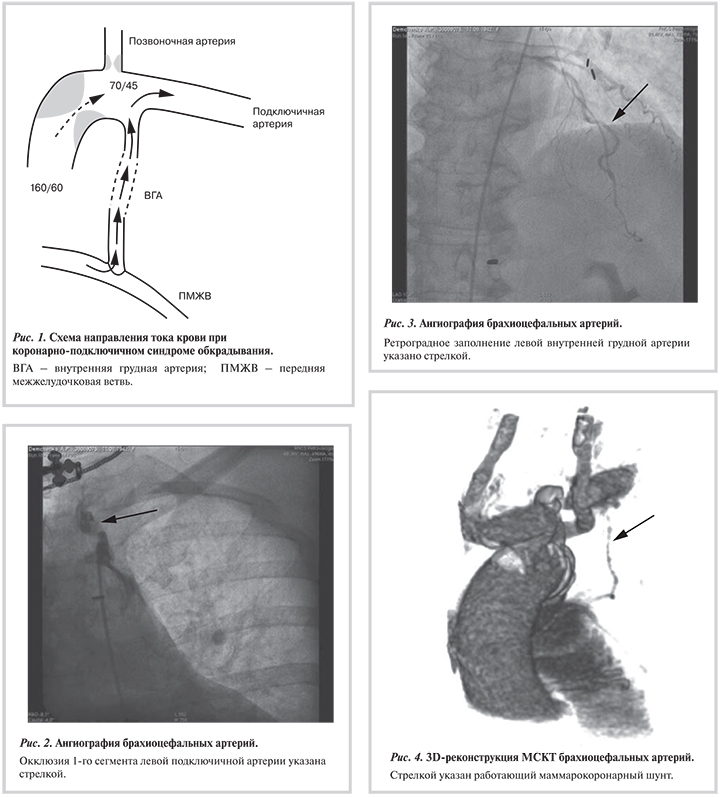

Развитие проксимального стеноза или окклюзии подключичной артерии может приводить к обратному току крови в левой ВГА, что ведет к возврату стенокардии и сердечной недостаточности (рис. 1). Впервые данная клиническая ситуация была описана в литературе в 1974 г. P.T. Harjola, M. Valle и названа коронарно-подключичным синдромом обкрадывания [5, 6].

При ангиографии и шунтографии в обоих случаях были выявлены окклюзия I сегмента левой подключичной артерии и ретроградное заполнение левой ВГА (рис. 2, 3). Пациентам было выполнено сонно-подключичное шунтирование из надключичного доступа с использованием синтетического протеза. Длительность ишемии головного мозга составила 8 и 17 мин соответственно. Кровопотеря в обоих случаях не превышала 100 мл. Послеоперационный период протекал гладко, пациенты выписаны на 5-е сутки после операции. Оба пациента в раннем послеоперационном периоде отмечали отсутствие стенокардии и повышение толерантности к физическим нагрузкам.

Синдром коронарно-подключичного обкрадывания является весьма редким, но достаточно известным явлением у пациентов, подвергшихся реваскуляризации миокарда с использованием левой ВГА [4]. Данный синдром может протекать бессимптомно для пациента, но может вызывать рецидив стенокардии, ишемию левой руки, инфаркт миокарда и прогрессирование сердечной недостаточности, а также появление транзиторных ишемических атак. Ангиография дуги аорты и брахиоцефальных артерий является «золотым стандартом» в диагностике данного синдрома [8]. Альтернативой в диагностике коронарно-подключичного синдрома обкрадывания могут служить ультразвуковое сканирование брахиоцефальных артерий и мультиспиральная компьютерная томография [9] (рис. 4).